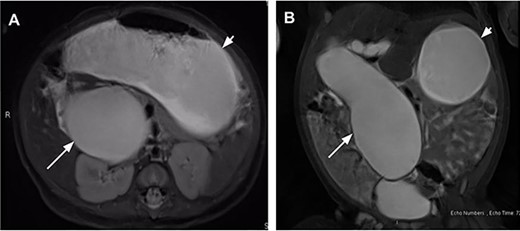

On DOL 22, the patient presented for a routine outpatient follow-up. She was tolerating feeds and stooling normally at home; her exam was unremarkable aside from mild abdominal distention. Laboratory results at that time showed TB 1.6 (0.3–1.2) and DB 0.8 (0–0.4). An magnetic resonance cholangiopancreatography (MRCP) was subsequently obtained on DOL 36 which revealed progression of the cyst, now measuring 5.1 × 4.2 × 10.8 cm, associated with a markedly distended stomach and decompressed small bowel (Fig. 1). The cyst was also observed to be displacing loops of bowel medially and inferiorly, exerting mass effect on the right kidney and extending into the pelvis where it was abutting the bladder. The patient was subsequently referred to the emergency department for admission and operative repair. Due to significant increase in size of the cyst on MRCP with impending GOO and cholestatic lab pattern (ALP 466, TB 2.1, DB 1.6), the patient was admitted for open CC excision at DOL 39. Exam on admission was significant for mild scleral icterus and abdominal distension with reported acholic stools. Notably, she was still tolerating feeds with no episodes of emesis.

Magnetic resonance cholangiopancreatography on day of life (DOL) 36 in coronal (A) and axial (B) views showing a massive fusiform dilatation of the common bile duct (long arrow) and markedly distended stomach (short arrow) consistent with gastric outlet obstruction.